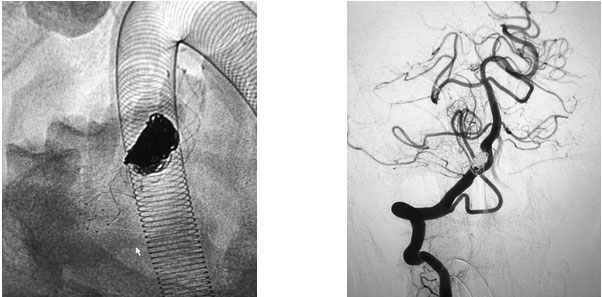

在充分准备后,张琪博士在刘春医生、周林华医生协助下为患者进行了支架辅助动脉瘤栓塞手术。填入弹簧圈后,再置入支架,完全释放后,造影显示动脉瘤无显影,支架覆盖良好,载瘤动脉通畅,撤出微导管输送系统,复查双侧椎动脉造影显示远端血流通畅。

▲ 术前影像

▲ 术后,造影显示动脉瘤无显影,栓塞成功